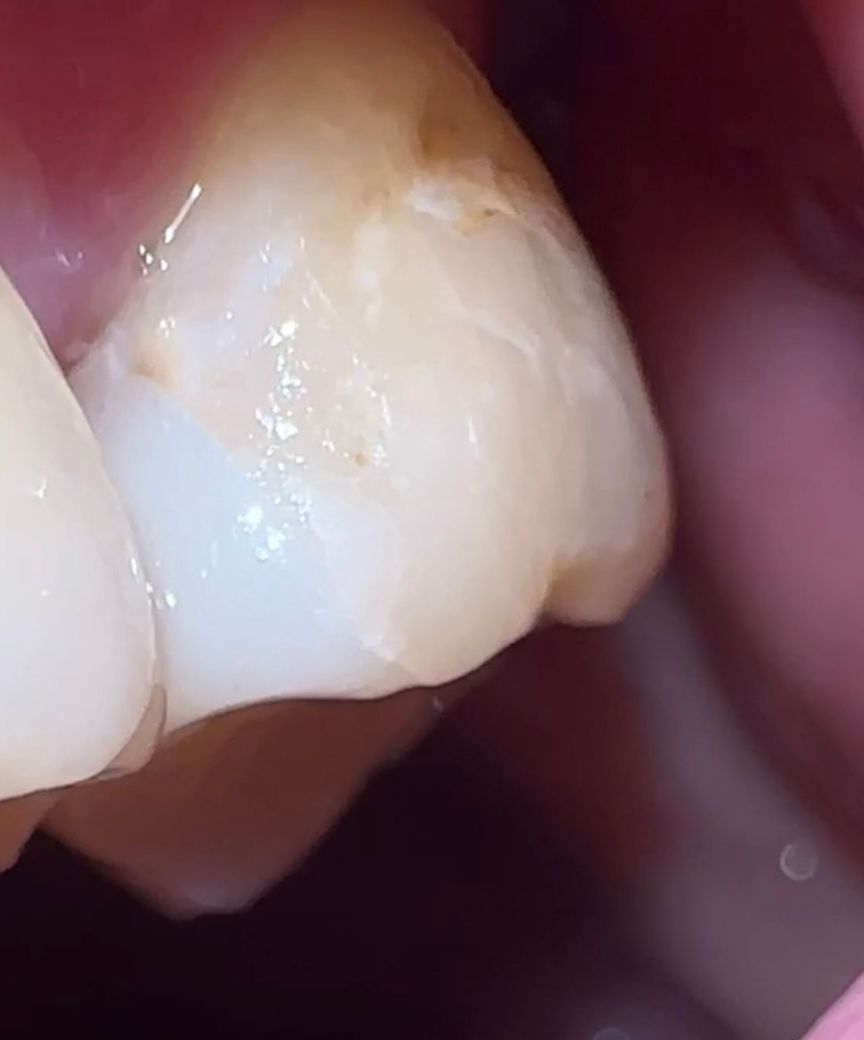

치아 파절!! 심각한건가여 아니면 금간걸까요

지르 인레이를 받고나서 가끔 양치질, 치실을 할때 이가 제자리에서 붕 뜨다가 다시돌아가는 느낌을 받습니다. 씹을때 아프지 않고 시린증상도 인레이 하고난 후 그 하루뿐, 이후로는 증상이 없습니다. 질문을 드리는이유는, 치실이 잘 안들어가서 사진을 찍어서 봤는데 제가 모르던 금들이 막 가있네요.

잔금이 너무 많아서 걱정입니다. 혹시 심각한 것일까요? 제가 유학생이라 이제 출국을 해야하는데 치료시기도 놓칠까 걱정입니다.

금이 간 것 처럼 보이진 않지만 인레이가 떨어진 것일수도 있으니 치과는 가보시는 게 좋겠습니다.

현재 인레이부분에 금이 가고 손상이 있는 것으로 보입니다. 이 경우 방치시 인레이탈락의 우려가 있기에 출국전에 치과에 방문하여 치료를 받길 권합니다.

인레이 자체는 문제가 없는거 같은데 치아가 선천적으로 약간 약한거 같습니다. 표면에 덜 강화되서 치아들이 조금씩 깨지는거 같습니다.

치아 표면에는 원래 잔금이 있을 수 있고 그게 크게 문제가 되진 않습니다. 다만, 딱딱하거나 질긴 음식에 대해 주의할 필요는 있습니다. 아직까지 별다른 증상이 없다면 인레이를 교체하거나, 추가적으로 치아에 크라운을 씌워주거나 그러진 않아도 됩니다.